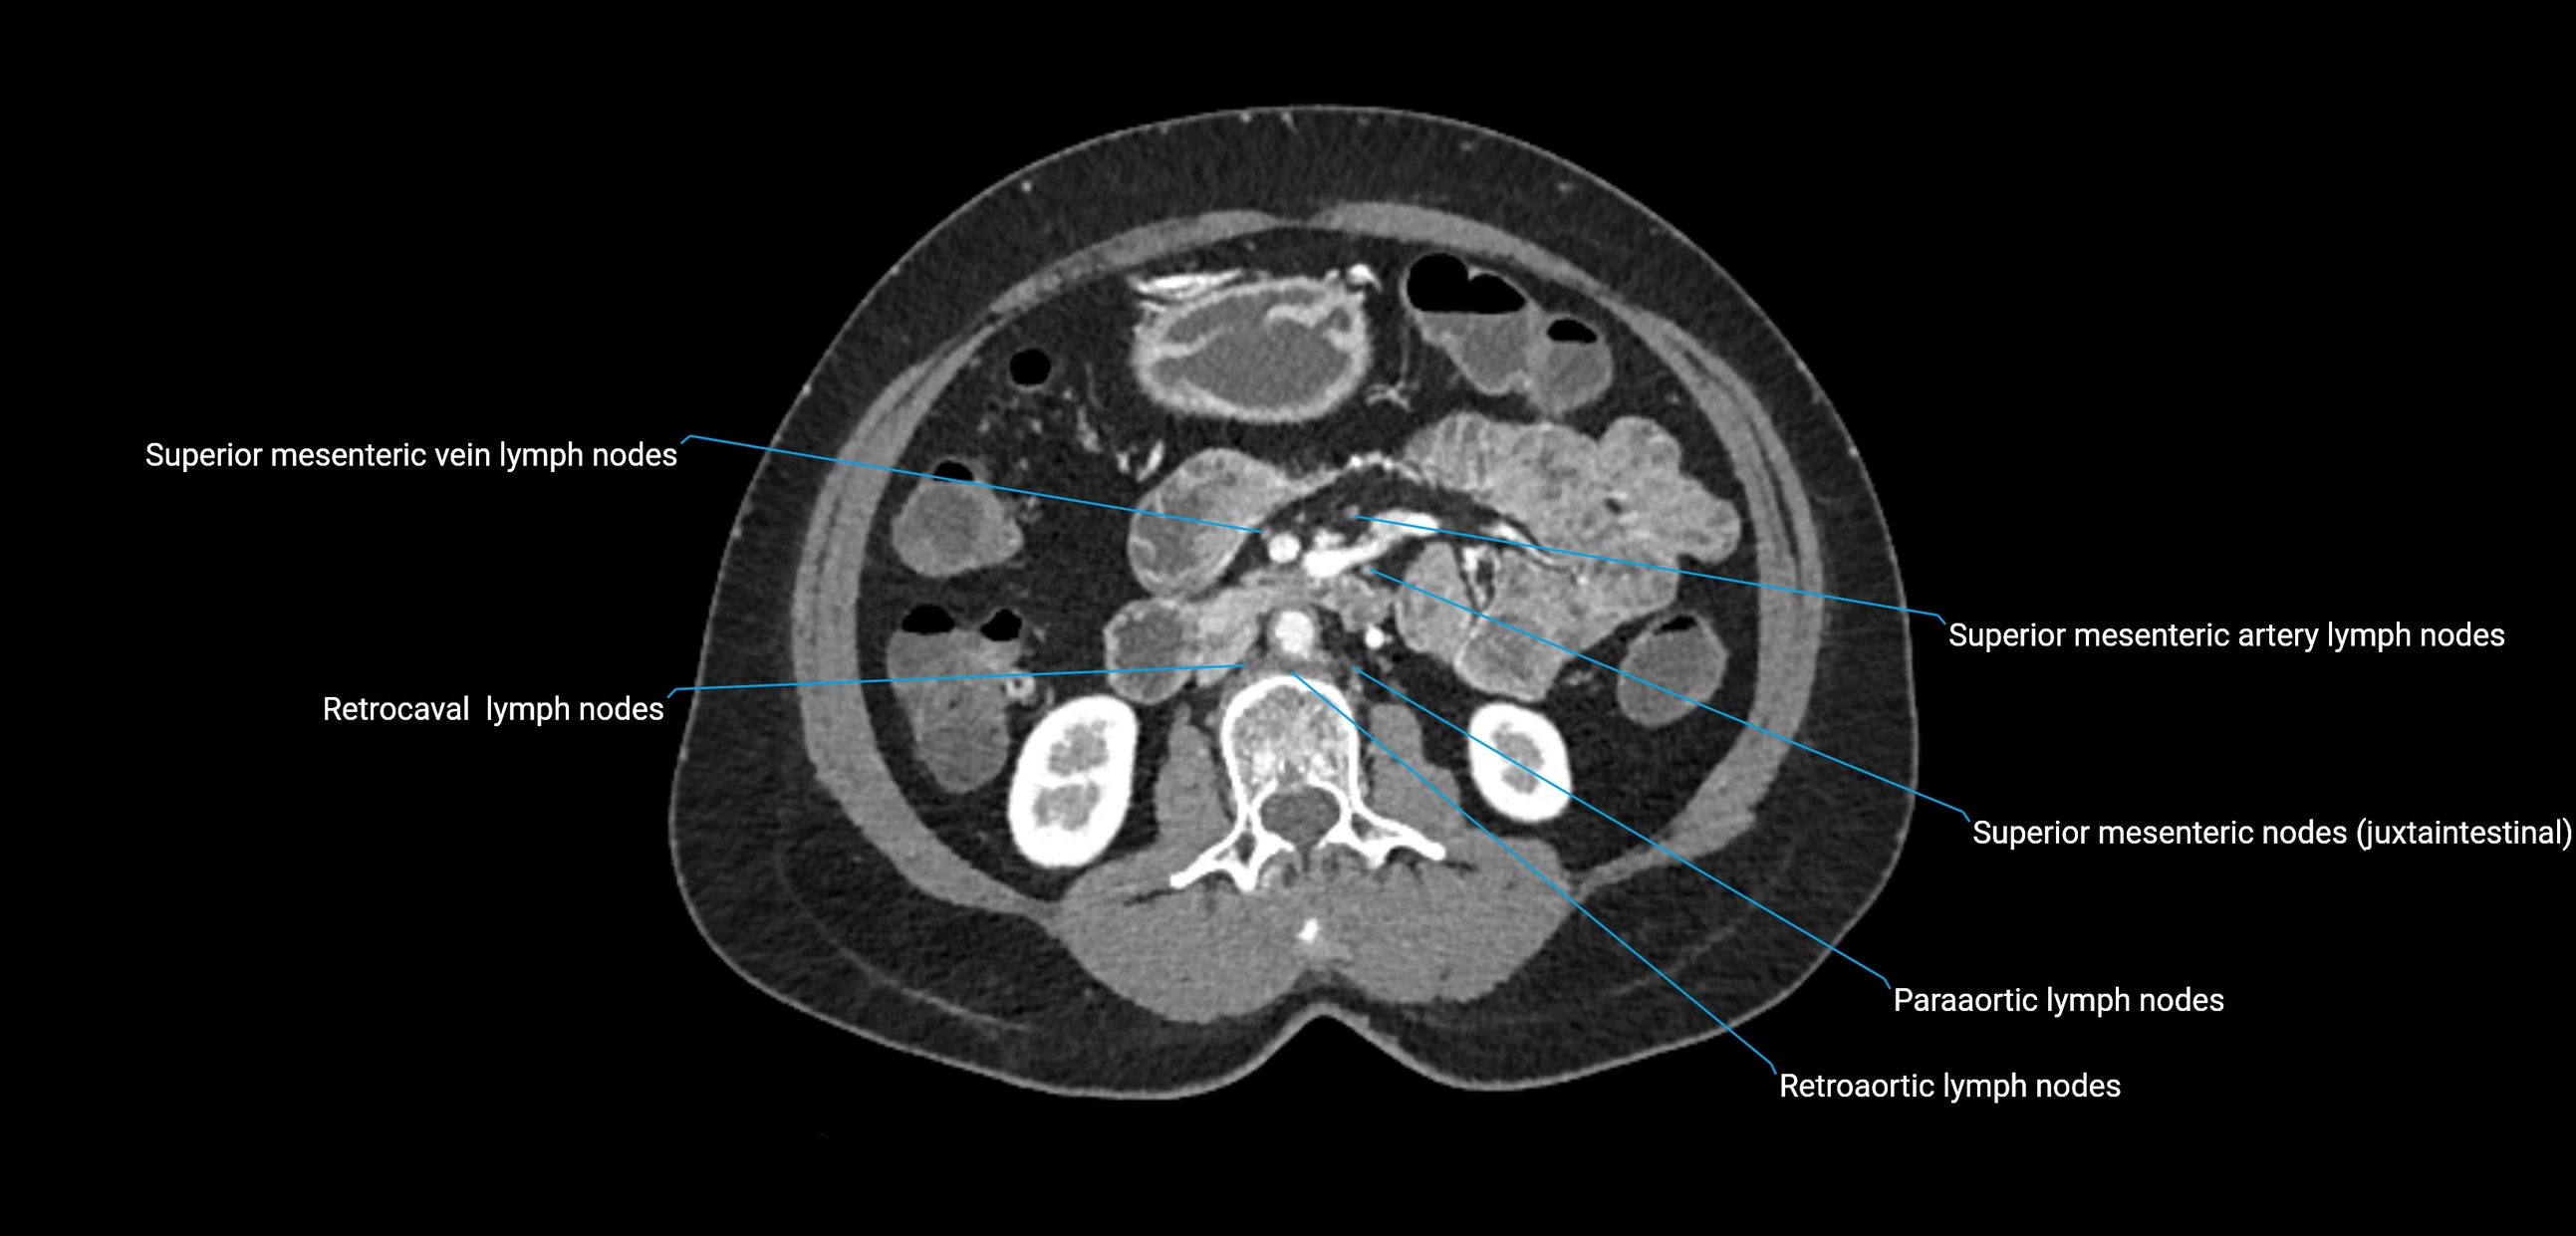

CT Appearance

CT Pre-Contrast:

• Nodes appear as soft-tissue density nodules adjacent to the aorta and IVC

• Calcification may be seen in chronic infections (e.g., tuberculosis)

CT Post-Contrast:

• Normal nodes enhance homogeneously

• Malignant nodes may show heterogeneous enhancement, central necrosis, or conglomerate formation

• Size >1 cm short axis is suspicious, though morphology and distribution are equally important

CT Venography (CTV):

• Demonstrates nodal encasement or compression of adjacent vessels (aorta, IVC, renal veins)

• Useful in staging testicular and ovarian malignancies

• Provides 3D reconstructions for retroperitoneal lymph node dissection planning

CT image

image